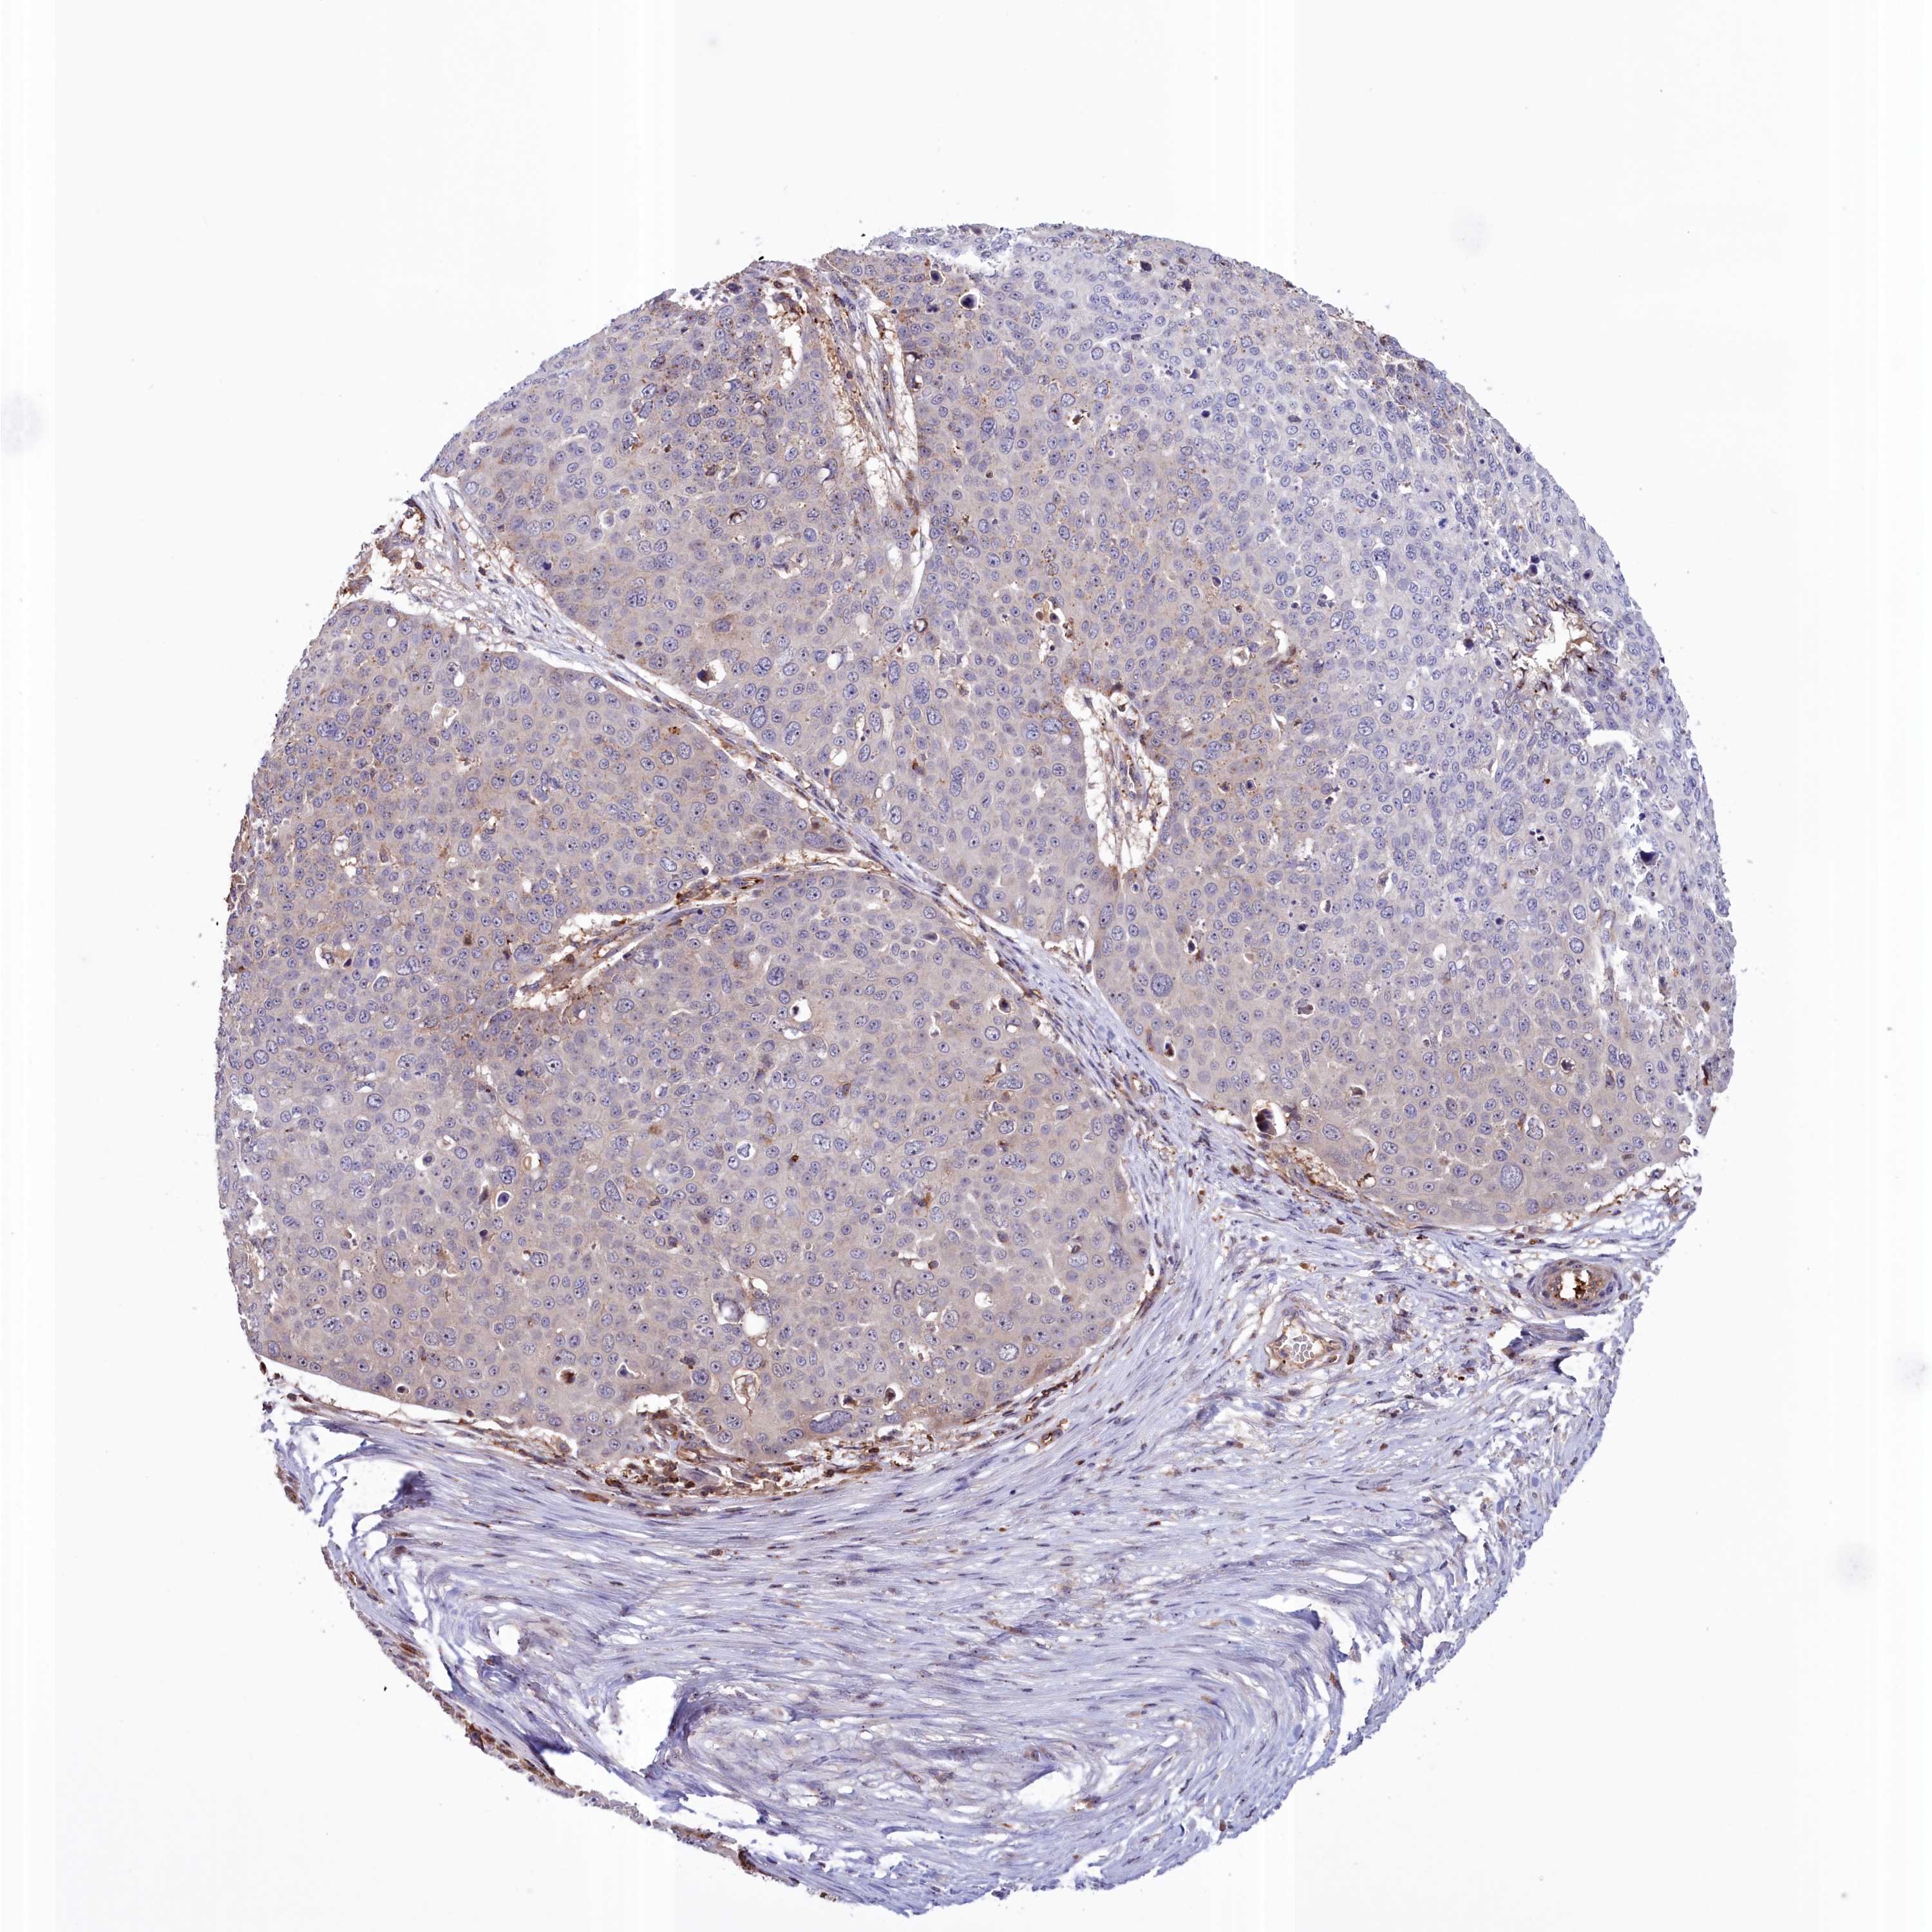

SKIN CANCER - Protein expressioni

A mouse-over function shows sample information and annotation data. Click on an image to view it in a full screen mode. Samples can be filtered based on level of antibody staining by selecting one or several of the following categories: high, medium, low and not detected. The assay and annotation is described here.

Antibody stainingi

Antibody staining in the annotated cell types in the current human tissue is reported as not detected, low, medium, or high, based on conventional immunohistochemistry profiling in selected tissues. This score is based on the combination of the staining intensity and fraction of stained cells.

Each image is clickable and will lead to virtual microscopy that enables deeper exploration of all samples and also displays staining intensity scores, fraction scores and subcellular localization as well as patient and tissue information for each sample.

Antibody HPA043678

Basal cell carcinoma